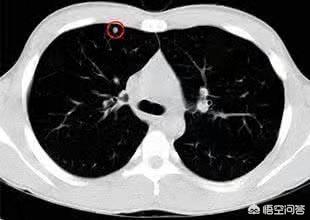

Im Allgemeinen müssen Knötchen mit einem Durchmesser von mehr als 8 mm genau beobachtet werden, insbesondere wenn sie unregelmäßig geformt sind oder sogar von einem gratartigen Muster begleitet werden oder mit Leere vermischt sind, an die Pleura angrenzen und als pleurale Vertiefungen erscheinen, sollten wir sehr wachsam auf die Möglichkeit einer Bösartigkeit sein. Falls erforderlich, ist eine Punktionsbiopsie oder eine direkte Exzision erforderlich.

Erstens werden bei der Einteilung der Lungenknötchen derzeit Lungenknötchen ≥8 mm und ≤3 cm als typische Lungenknötchen bezeichnet, während nur Lungenknötchen <8 mm als kleine Knötchen bezeichnet werden!

1. feste Knoten mit einem Durchmesser von mindestens 1,5 cm oder 8-15 mm, aber mit Anzeichen von Bösartigkeit;

2. sub-solide Lungenknötchen mit einem Durchmesser von mehr als 8 mm (gemischte Glasknötchen).

Bei dieser Frau mittleren Alters mit einem 2,2 cm großen Mischmembran-Glasknoten in der linken unteren Lunge handelt es sich beispielsweise um einen Hochrisikoknoten, der in der Tat die klassischen Anzeichen eines Lungenadenokarzinoms aufweist, zu denen gehörenGut ausgeprägter Mattigkeitsschatten mit Gefäßeintritt und Verdickung, bronchiales Insufflationszeichen, distale Pleurabeteiligung, chirurgische Pathologie eines invasiven LungenadenokarzinomsDiese Art von Läsion wird nicht zur Nachsorge empfohlen und sollte zur Abklärung weiter untersucht werden, um eine Metastasierung und eine verzögerte Behandlung zu vermeiden.